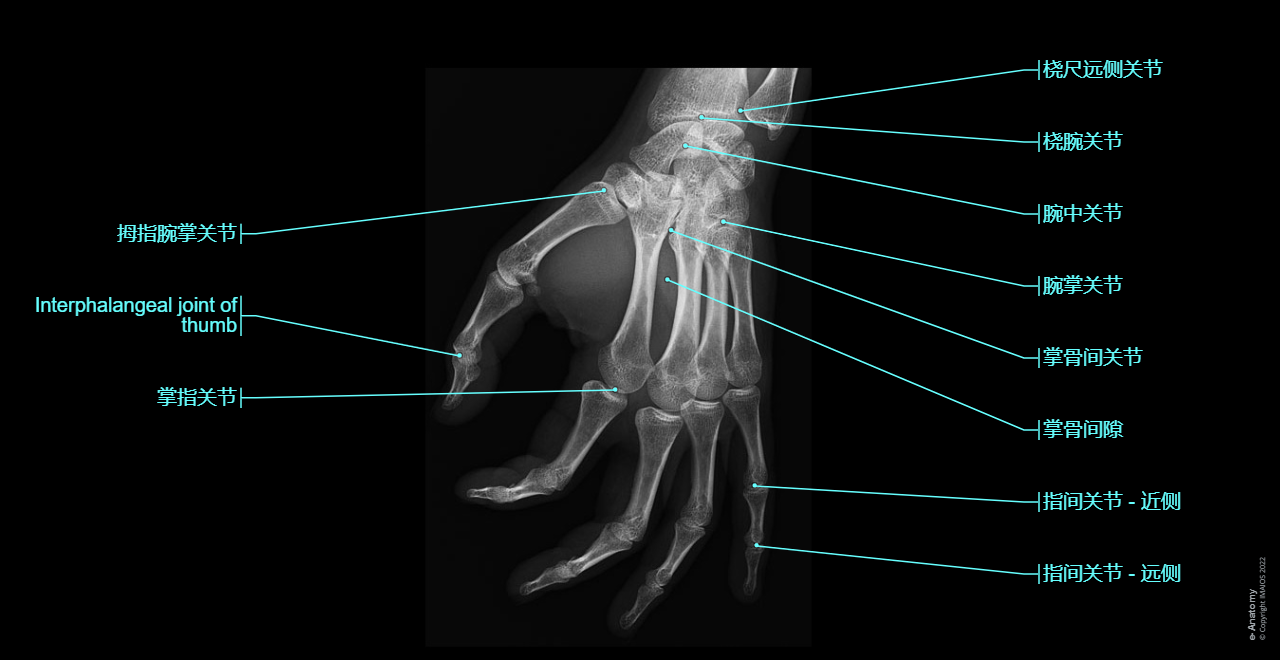

手部和手指X光照片:斜视图